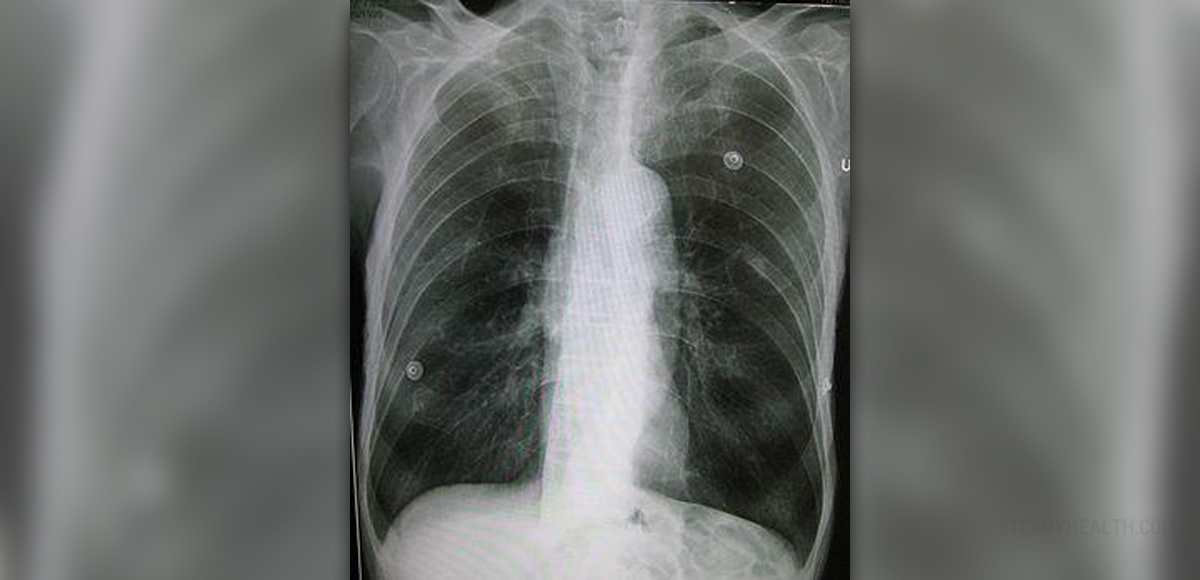

What is the best test for emphysema?

This means that air is being trapped in your lungs. Other tests include: X-rays: X-rays are generally not useful for detecting early stages of emphysema.

Once the test is completed, the readings are compared to X-rays of healthy or normal lungs. Pulse oximetry: This test is also known as an oxygen saturation test.